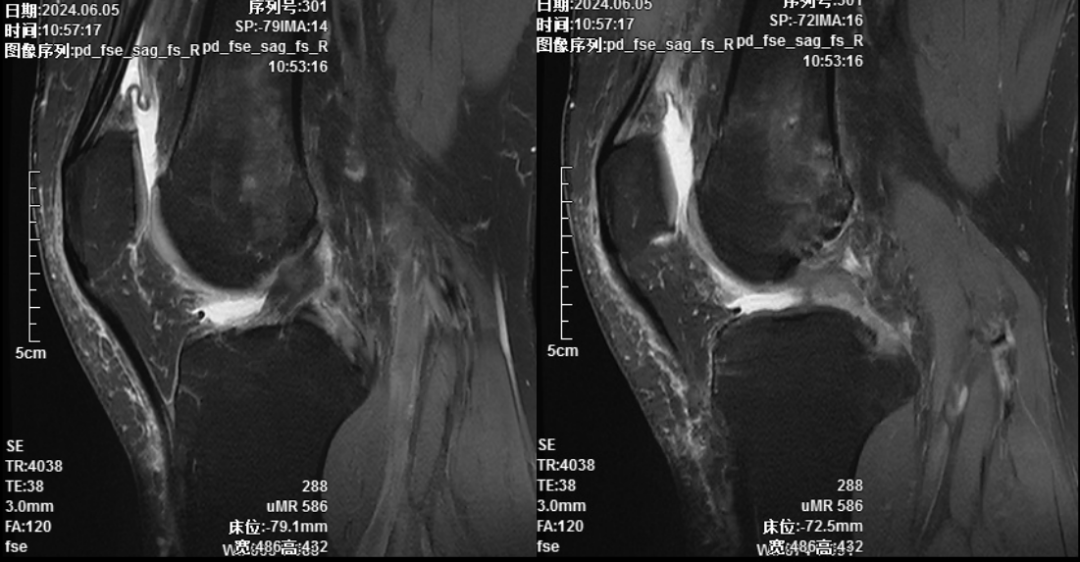

术前核磁共振提示膝关节后交叉韧带断裂